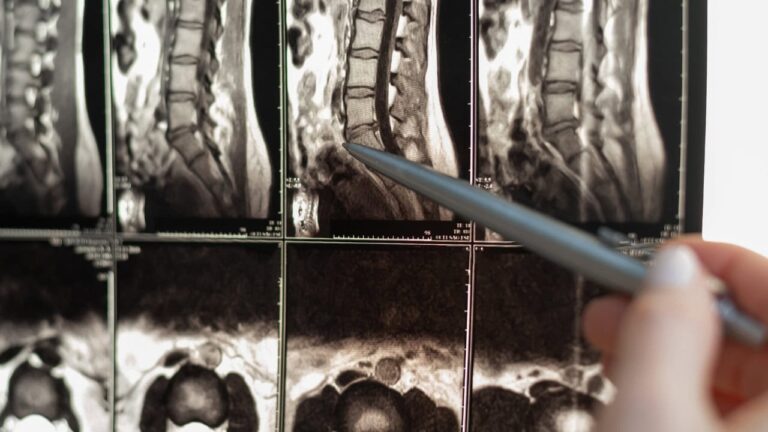

Em alguns casos, as neuropatias de aprisionamento surgem na coluna vertebral, como nas radiculopatias cervicais ou lombares. Essas condições ocorrem quando as raízes nervosas são comprimidas, geralmente devido a hérnia de disco ou alterações degenerativas na coluna vertebral. Embora esses distúrbios possam parecer distintos, eles compartilham o mecanismo subjacente de compressão ou irritação do nervo, levando a uma variedade de sintomas sensoriais e motores.

Ferramentas avançadas de diagnóstico, como ressonância magnética e eletrodiagnóstico, são úteis para confirmar o diagnóstico em casos complexos. A RM é útil para identificar alterações estruturais nos tecidos que provocam neuropatias, enquanto os estudos de condução nervosa podem avaliar o status funcional dos nervos afetados. Esse momento representa um desafio significativo, pois as enxaquecas ocorrem predominantemente quando os indivíduos estão concentrados em suas carreiras, no trabalho e na criação dos filhos. Depois de atingir esse pico, muitas pessoas experimentam um declínio gradual na frequência das enxaquecas à medida que envelhecem, especialmente as mulheres, que podem notar uma redução nas ocorrências de enxaqueca por volta da menopausa.

O futuro do diagnóstico e do tratamento da neuropatia por aprisionamento é promissor, graças aos avanços na geração de imagens e na medicina de precisão. A RM de campo ultra-alto e a neurografia por RM estão abrindo caminho para diagnósticos mais precisos, permitindo que os médicos visualizem os nervos com detalhes sem precedentes. Essas técnicas são particularmente valiosas para identificar alterações sutis na estrutura do nervo que podem não ser visíveis com a imagem tradicional.